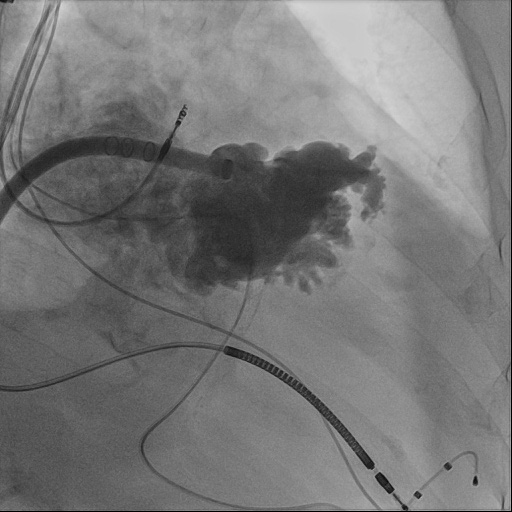

心血管内科团队与超声诊断科、麻醉科进行了术前会诊,对钟婆婆病例进行研讨分析,制定了周密手术方案及并发症应急预案。术中唐波副主任医师与沈松林主治医师通力合作,经右侧股静脉,在食道超声引导下穿刺房间隔,将长鞘顺利进入患者左心耳,利用猪尾导管进行造影,同时进行测量,选择合适的封堵器封堵左心耳。术中,超声诊断科为钟婆婆实时进行经胸、经食道超声心动图检查,以实时精密的测量为手术医师提供有效可靠地帮助;麻醉团队为钟婆婆诱导麻醉、气管插管、全麻和机械通气及全程监测,各学科通力配合,顺利完成手术。

图2、经左心耳封堵器鞘管进行左心耳造影,结合食道超声测量左心耳大小,选择合适的左心耳封堵器。